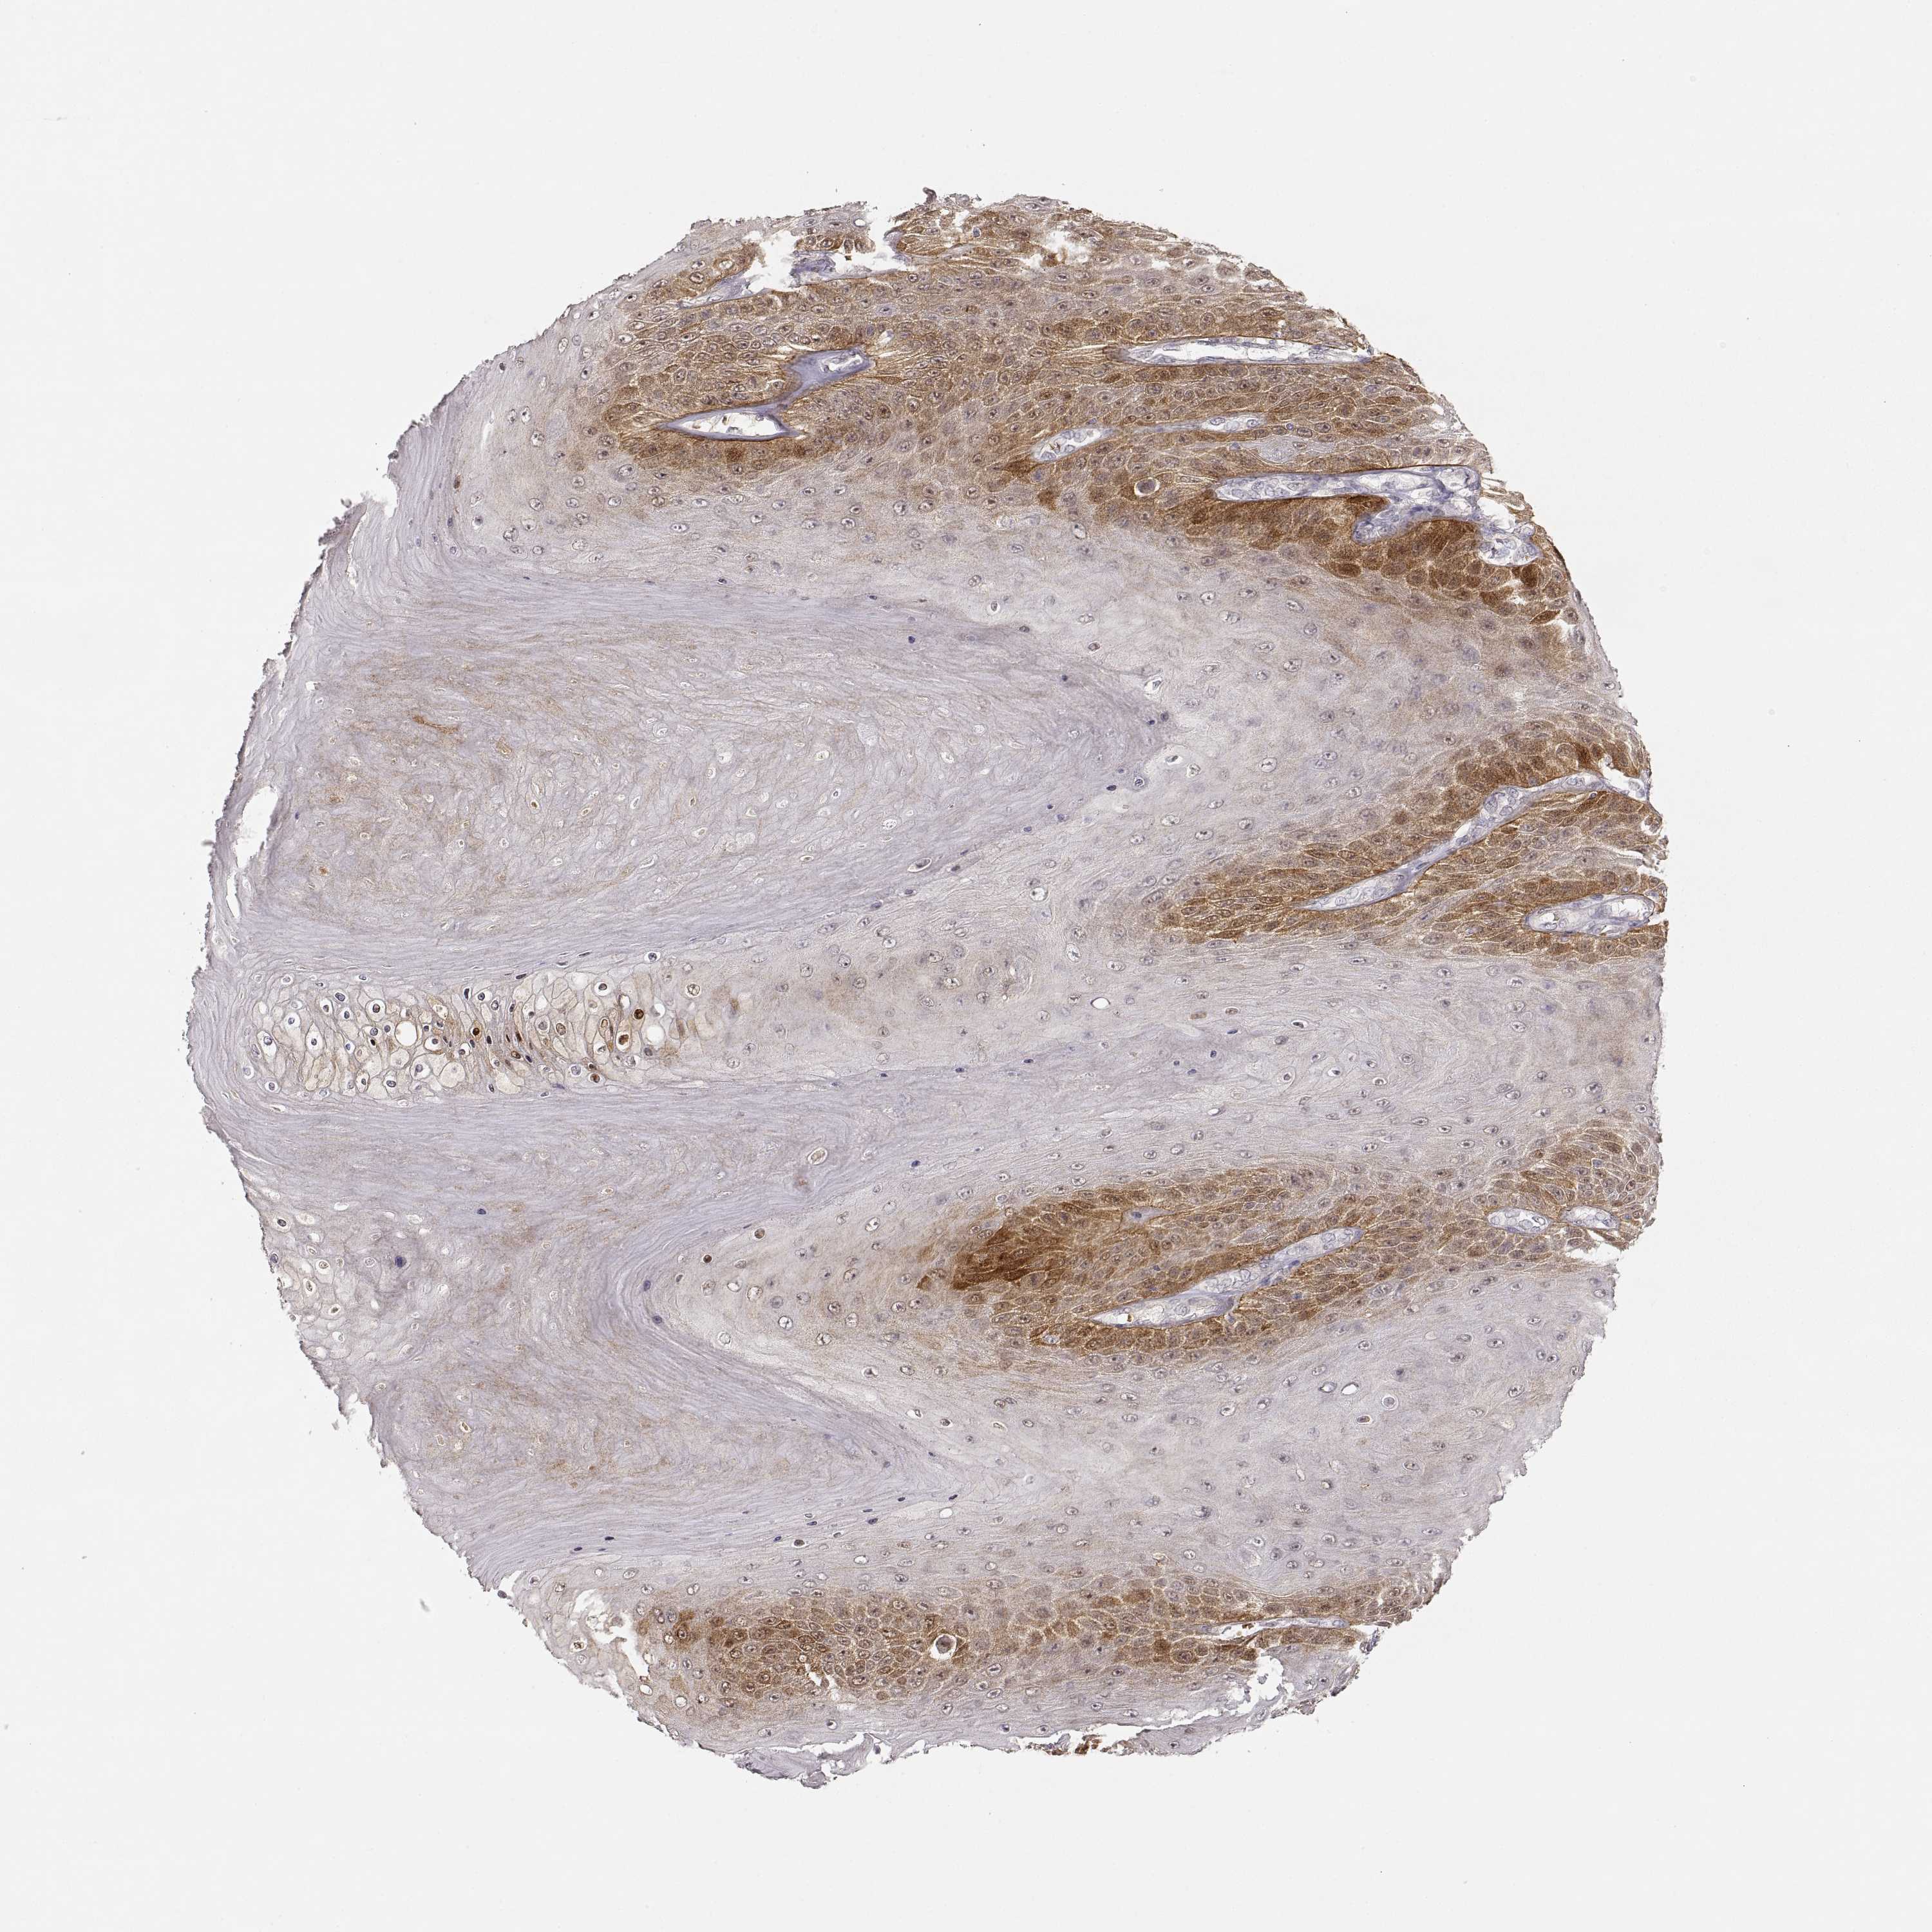

CANCER SKIN CANCER Show tissue menu

Basal cell and squamous cell cancer

SKIN CANCER - Protein expressioni

A mouse-over function shows sample information and annotation data. Click on an image to view it in a full screen mode. Samples can be filtered based on level of antibody staining by selecting one or several of the following categories: high, medium, low and not detected. The assay and annotation is described here.

Each image is clickable and will lead to virtual microscopy that enables deeper exploration of all samples and also displays staining intensity scores, fraction scores and subcellular localization as well as patient and tissue information for each sample.

Antibody CAB078165

Squamous cell carcinoma, NOS